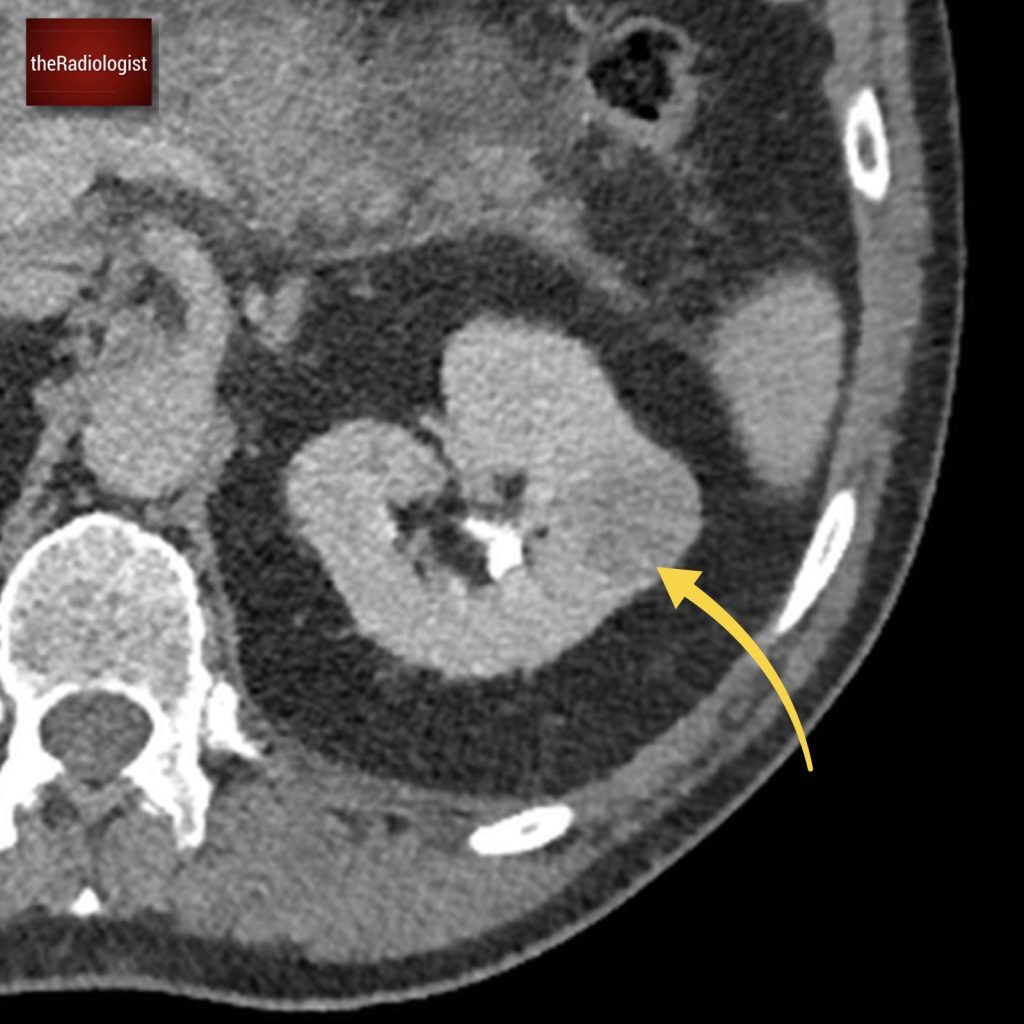

Due to pain the patient could only tolerate a few STIR sequences so we don’t have a complete scan but have a look at this axial STIR sequence below. We have high STIR signal within the right psoas with locules suggesting abscess formation.

Have a look at this axial STIR image from the MRI scan. Here we have high SITR signal within the right psoas with locules suggesting abscess formation.

If we look at a lateral STIR sequence of the lumbar spine, we can see high signal in the lateral aspect of the L3-4 disc which is continuous with the abscess formation within the right psoas. This highly suggests a spondylodiscitis as the primary pathology leading to secondary psoas abscess.

When we scroll through this sagittal STIR sequence of the lumbar spine we will see high signal within the L3-4 disc adjacent to the right psoas abnormality.